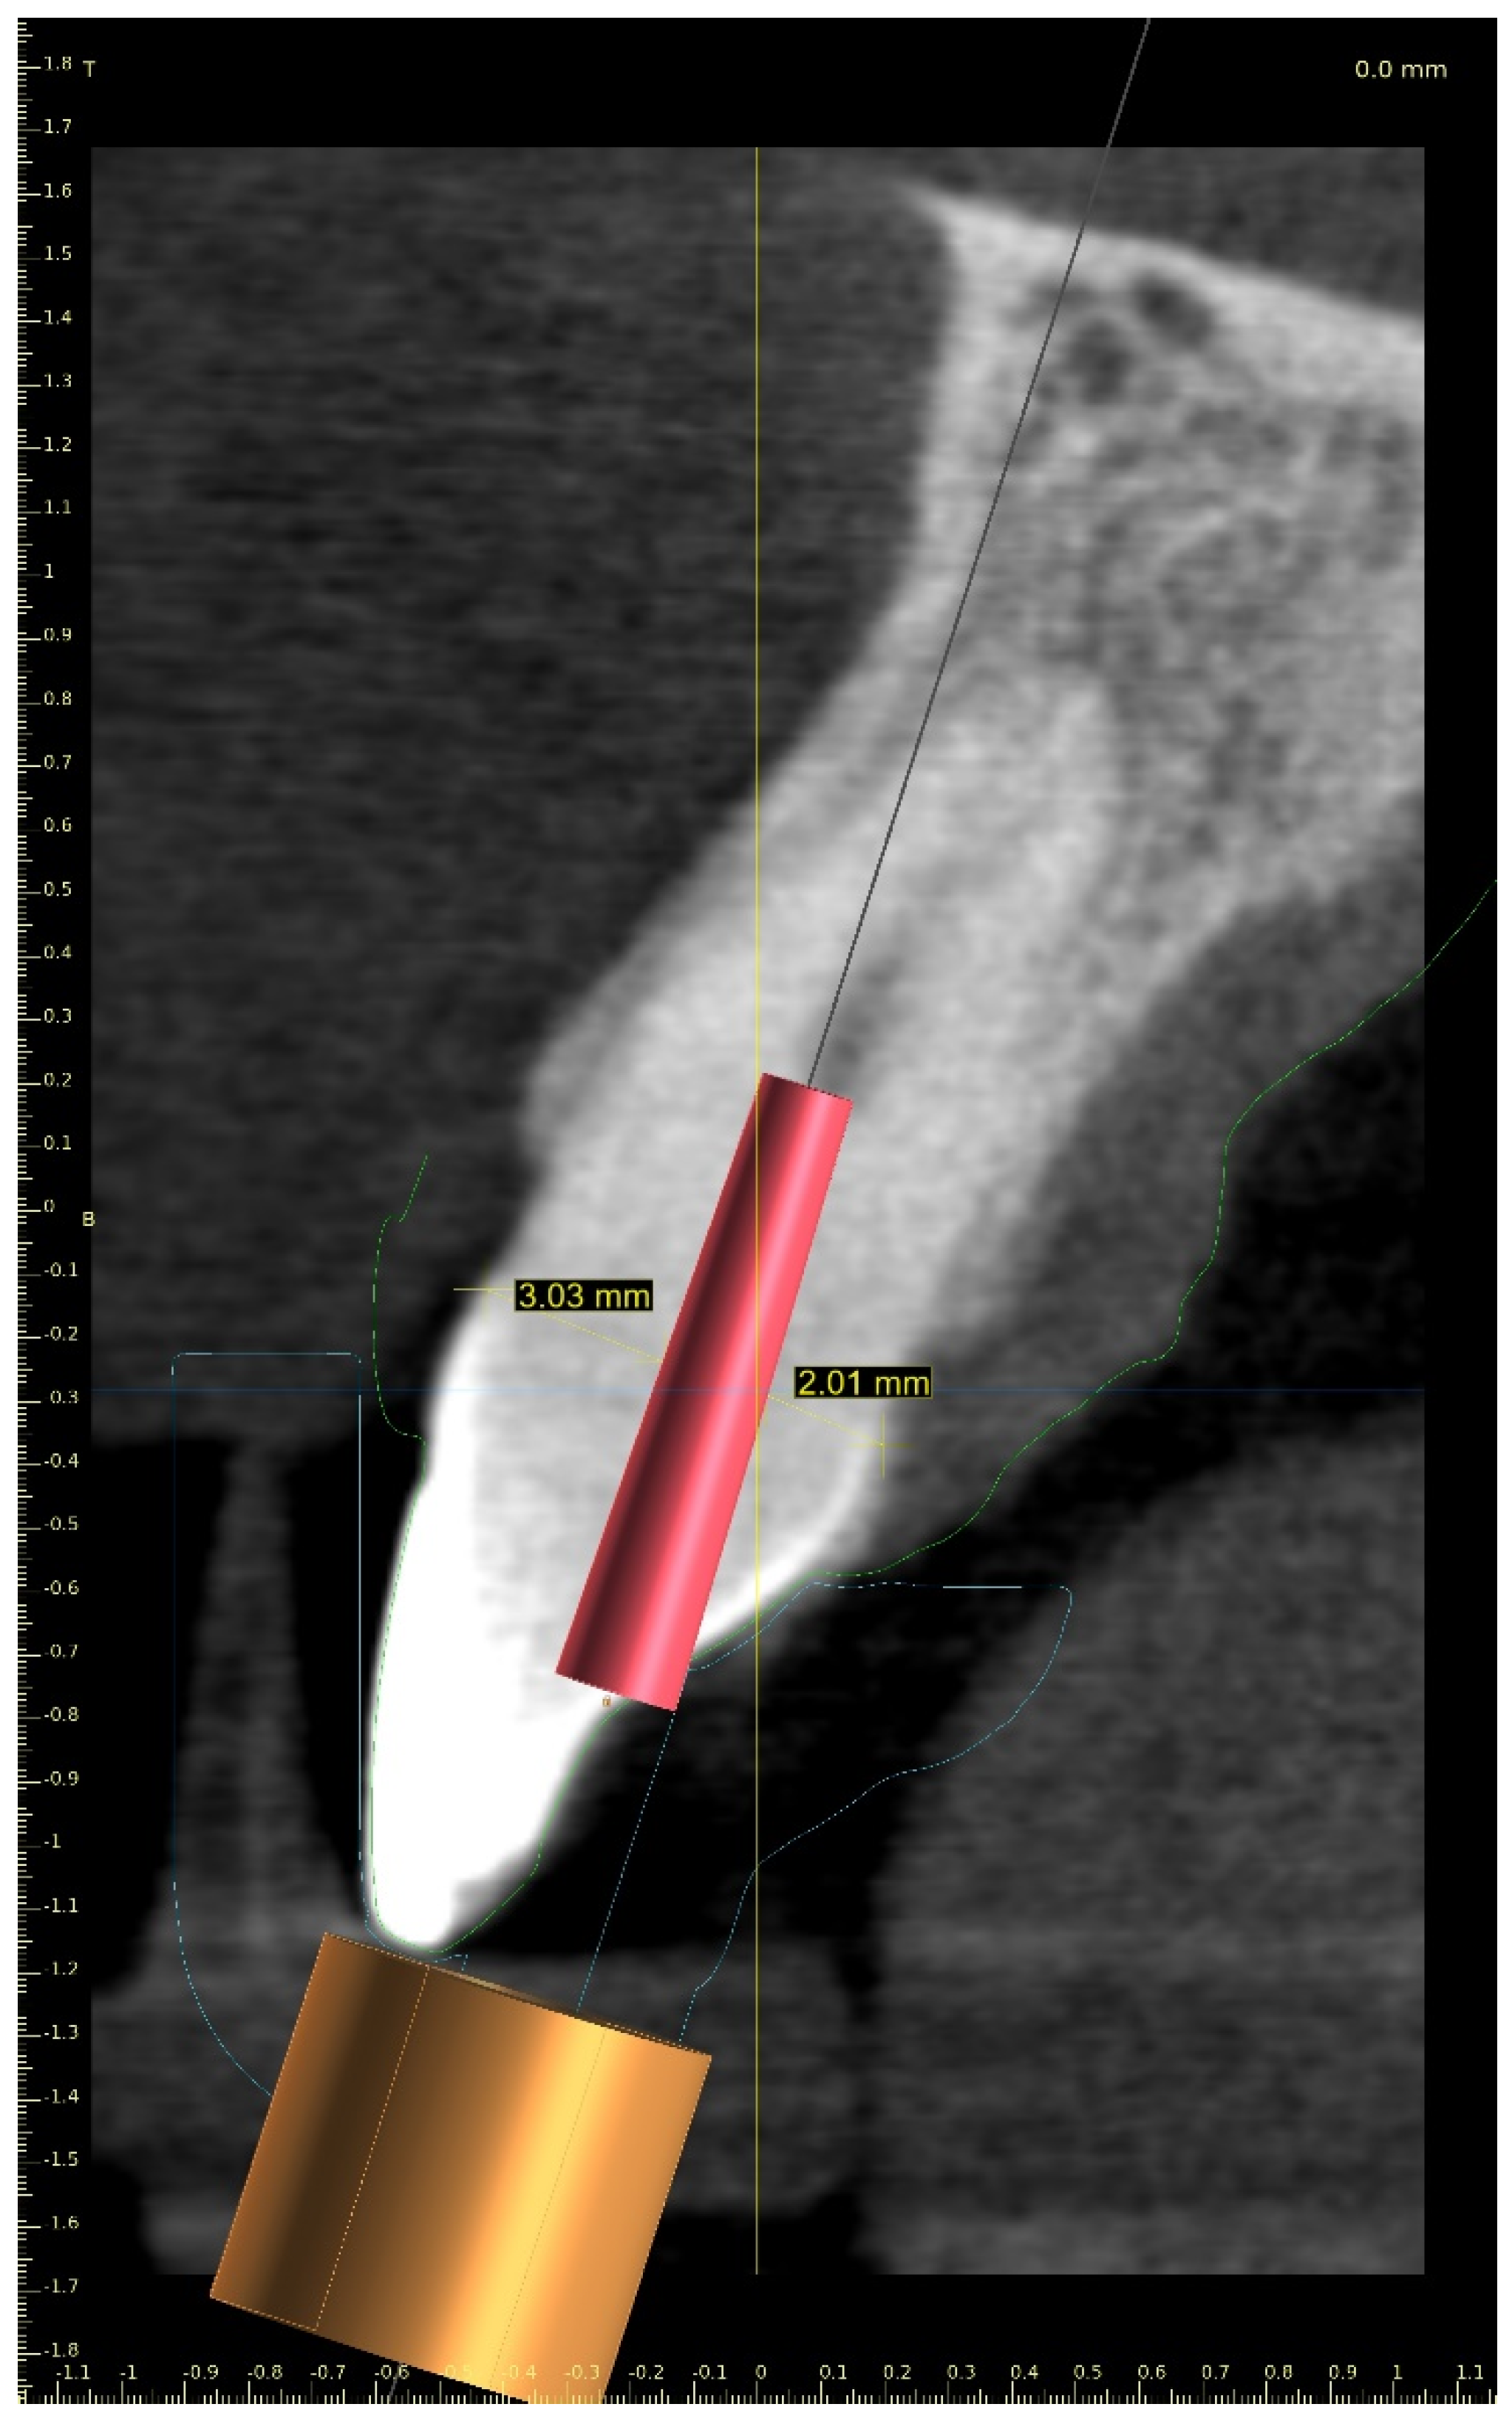

Three-Dimensional Treatment Plan

Three-Dimensional Treatment Plan and RCT